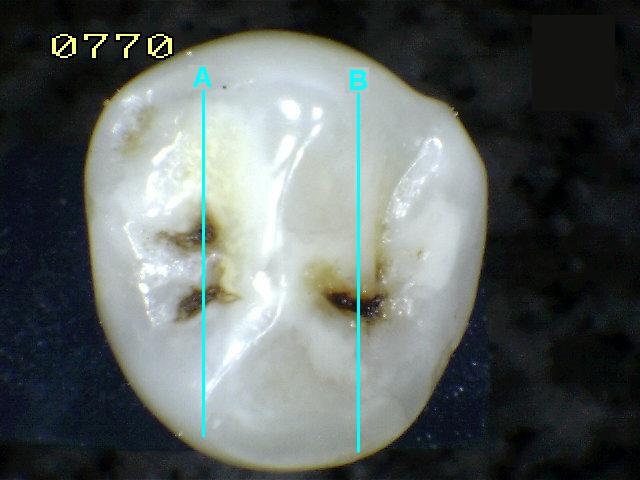

Espécimen Nº

36 |

| Corte sagital A:

Código 0

histológico |

Corte sagital B : Compatible con

código 1